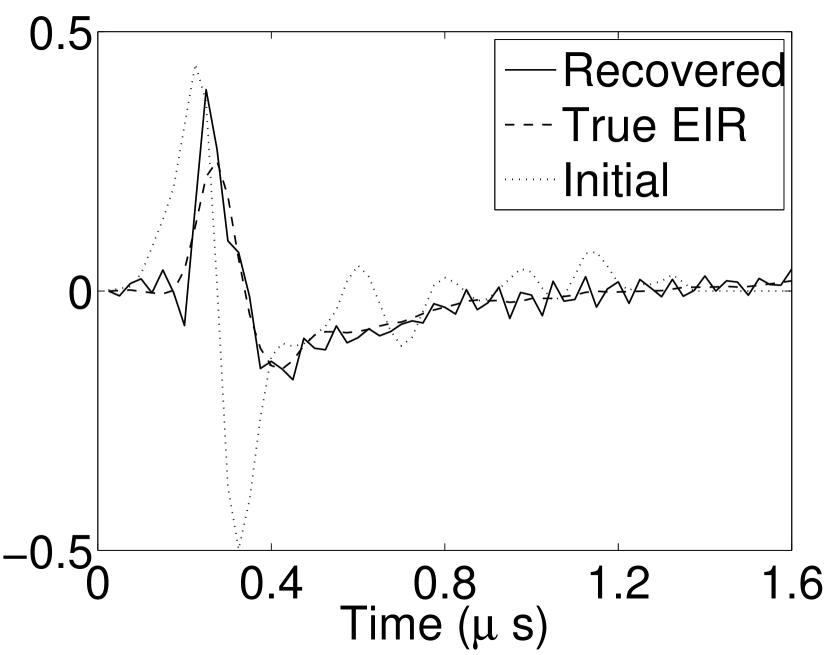

Figure 7(a) reveals that use of the inaccurate EIR in the conventional iterative method created strong artifacts and distortions. Figures 7(b) confirms that the artifacts and distortions were significantly mitigated when the VP method was employed. Image profiles for both cases are shown in Figures 7(c). The overall accuracy of the recovered EIR, shown in Figure 7(d) and 7(e), was improved, but it contained spurious oscillations.

Images reconstructed by use of the VP algorithm with different values of the regularization parameter values are shown in Figure 8. The recovered EIRs and their corresponding Fourier spectra are shown in Figures 9 and 10, respectively. The RMSE values are computed and displayed together with the corresponding images. As expected, the images reconstructed with smaller values of contain higher noise levels, while images using larger possess a reduced noise level. However, larger values of also caused artifacts in the reconstructed images. The same observation can be made for the effect of the regularization parameter on the recovered EIR. One also observes that the reconstructed images and EIRs depend continuously on the regularization parameters and , i.e. small changes in the regularization parameters cause minor changes in the reconstructed images and EIRs.